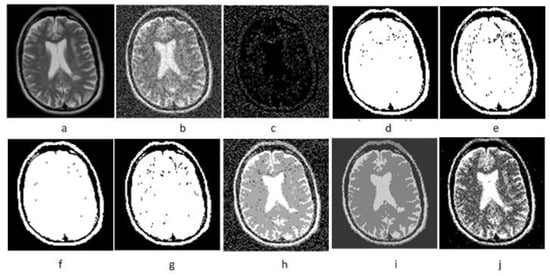

4.3.1. Denoising Experimental Results of MR Image